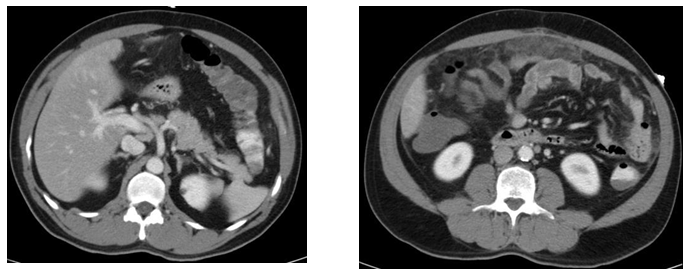

The CT thorax and CT pulmonary angiogram showed marked pulmonary infiltrates and thrombi. There was a thombus in the segmental right lower lobar pulmonary area, with an infracted region in the right lung base. There was also another thrombus in the anterior segmental branch of the left lower lobe pulmonary artery. Subsequently, the patient suffered from opthalmoplegia due to stroke in the ward. The MRI/MRA revealed acute infarcts in the left cerebellum, occipital lobe and left medial longitudinal fasciculus. He also developed gut vasculitis and a perforated transverse colon (Figure 3) (Figure 4). The findings on CT abdomen and pelvis were consistent with that of a small/medium vessel vasculitis. Multifocal ischemic colitis was seen involving the right lateral and posterior walls of the rectum as well as the inferior wall of the mid transverse colon with suggestion of perforation on both sides. The superior rectal artery was thrombosed as well. The patient then underwent emergency laparotomy with resection of small bowel and stoma creation. Post-operatively recovered well and was discharged two weeks after. Currently he is on follow up with rheumatologist, neuroopthalmologist and general surgeon (Figure 5).

Figure 3 CT abdomen and Pelvis.

1. NON- specific long segment thickening of the rectal wall; soft tissue and extensive fat stranding are seen in t he mesorectum. Omental fat stranding is most promi nent in the upper abdomen abutting the anterior wall of transverse colon; thickening of the anterior transverse colon wall abutting the omental stranding.

2. 0.6cm splenenculi are seen in close relation to the anterior pole of the spleen.

3. A 1.6x1.2cm enlarged celiac node is noted.

4. Small volume, but round lymph nodes are seen along the inferior mesenteric artery and the para -aortic region, the largest in the para- aortic region measures 0.9x0.8cm.